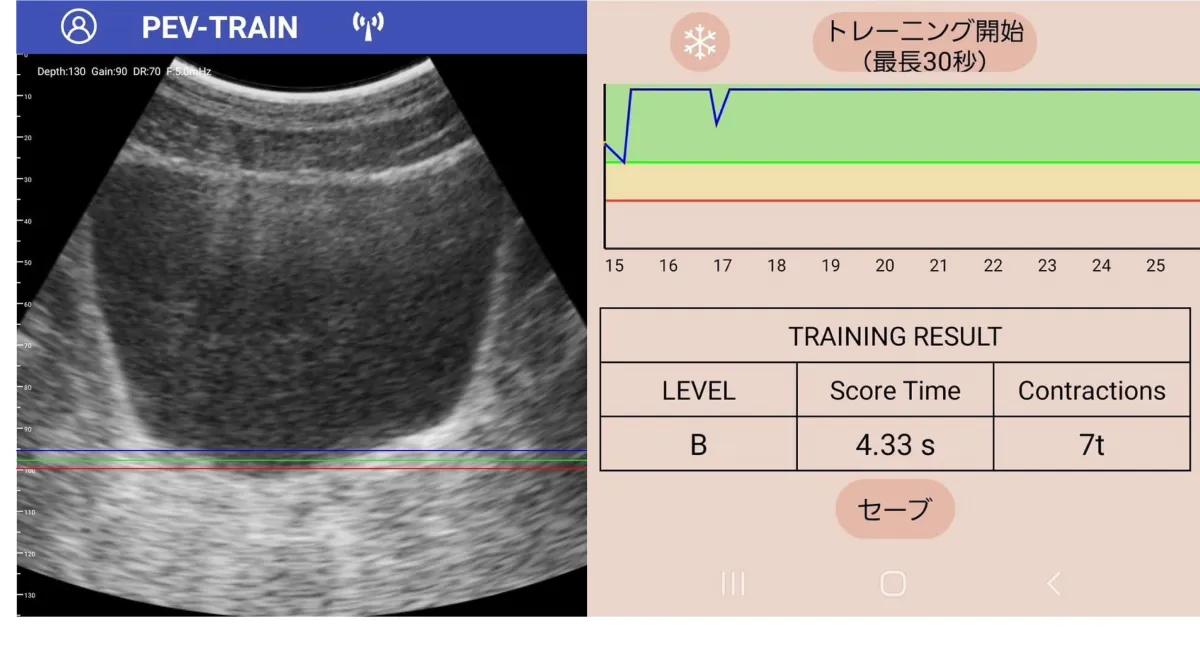

「PEV・TRAIN -ぺブトレ」は、自分の骨盤底筋の様子をスマホを通して視覚的に確認できます。従来の方法では、専門クリニックに足を運ぶ必要があり、時間もコストもかかってしまいますが、このアプリなら自宅で手軽にトレーニングができるのです。

自動計測機能

アプリは、「収縮幅」や「収縮時間」を自動的に記録し、トレーニングの成果を瞬時に把握できます。これにより、自分が正しく筋力を鍛えられているのかを確認しやすくなり、トレーニングへのモチベーションもアップします。

このアプリを使用するためには、iPhoneまたはAndroidスマートフォンが必要です。専用のスマホ・エコーをサブスクリプション形式でレンタルし、アプリをダウンロード。動画やマニュアルを参考にしながらトレーニングを開始することができます。トレーニングの結果はその場で画面に表示され、すぐに効果を実感することができるのです。